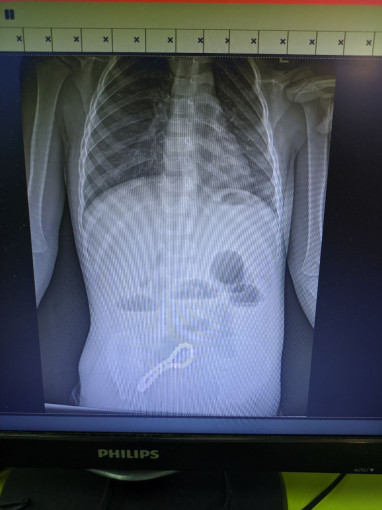

Ребенок попал в больницу с жалобами на проблемы с пищеварением. Медики предположили наличие в ЖКТ инородного тела, что подтвердил рентген.

«Было принято решение об операции. Мы провели минилапаротомию (хирургическое вмешательство, при котором через разрез передней брюшной стенки производится доступ к внутренним органам живота). И увидели, что магнитами, которые притянулись друг к другу, соединены петли кишки; в ее стенке отверстия. В ходе операции удалили все 30 магнитных бусин: 29 маленьких и одну большую», — рассказал хирург больницы Олег Ларькин.